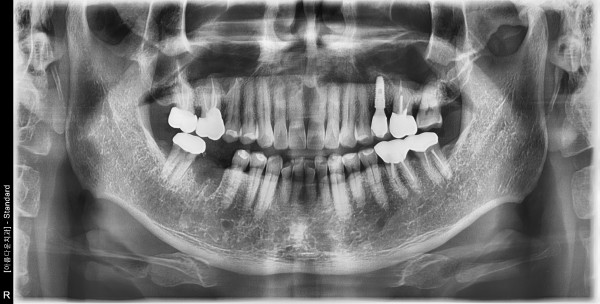

60대 남성 임플란트 식립